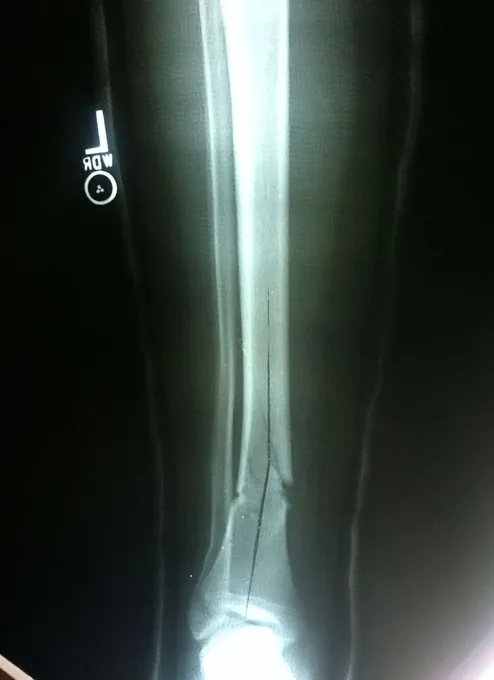

Below, Tibia and Fibula Fracture in a 16-year-old injured skiing. The patient presented to the office 8 days after injury with a displaced fracture. The first 2 films show the displacement in the fracture of the tibia. After an above knee cast is applied, the cast is wedged under fluoroscopy and new xrays show the near perfect reduction of the fracture. The white arrows show the area where the cast is wedged

Wedging of cast to keep a tibia fracture well aligned. We wedge the cast on a side if there is malalignment early on in the fracture healing to realign the fracture